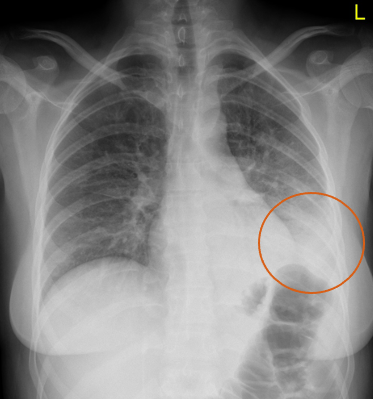

What does this CXR indicate? - Pneumoperitoneum - Pneumothorax - Pulmonary oedema - Consolidation - Pleural effusion

What does this CXR indicate? - Pneumoperitoneum - Pneumothorax - Pulmonary oedema - **Consolidation** - Pleural effusion